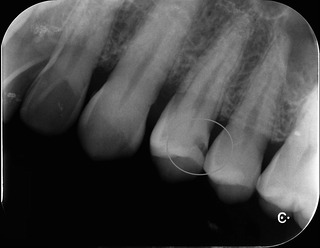

レントゲン

歯と歯の間に黒い病変が‥